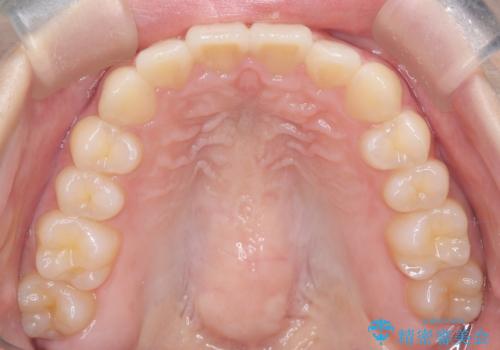

今回は抜歯矯正ではなく歯列弓の拡大とIPR、遠心移動を行って配列することができました。

口元も改善し患者さんには喜んでいただけました。

下顎前歯が1本少ないため、上下の正中は合いません。